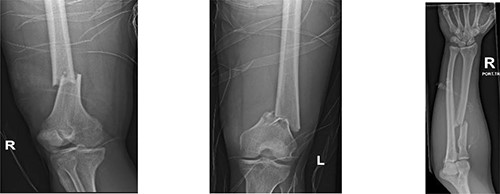

A 35-year-old male was severely injured by a truck tire explosion inside a mechanic garage. The EMS crew reported to the trauma team that the patient was found anxious, diaphoretic and hypotensive. Following fluid resuscitation, the patient was brought to the Level 1 trauma center. Upon admission, the patient’s initial vital signs were as follows: Glasgow coma scale: 15, blood pressure of 84/50 mmHg, heart rate of 117 beats/min; respiratory rate of 23 breaths/min and pulse oximetry of 99% under a reservoir mask oxygen flow of 10 l/min. There was tenderness and mild guarding in the right hypochondrium. Hemoperitoneum was identified on the focused assessment with sonography in trauma. Extremities examination revealed bilateral femur and right radius fracture (Fig. 1).

Radiographs show bilateral femoral and right radius fractures. R: right, L: left.